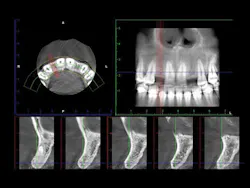

2. In the facial-lingual orientation, locate the osteotomies in the center of the ridge and parallel with the adjacent teeth. Use finger contact on the facial and lingual of the ridge while making the drill cuts. If you feel extra vibration on one or the other side of the ridge, reorient the drill appropriately (figures 4-7).

Figure 3: It is easy to center the implant osteotomy between the two adjacent teeth using your own clinical judgment and periapical radiographs.

Figures 4-7: This series of images shows a clinical situation, the cone beam images, and the freehand implant placement.